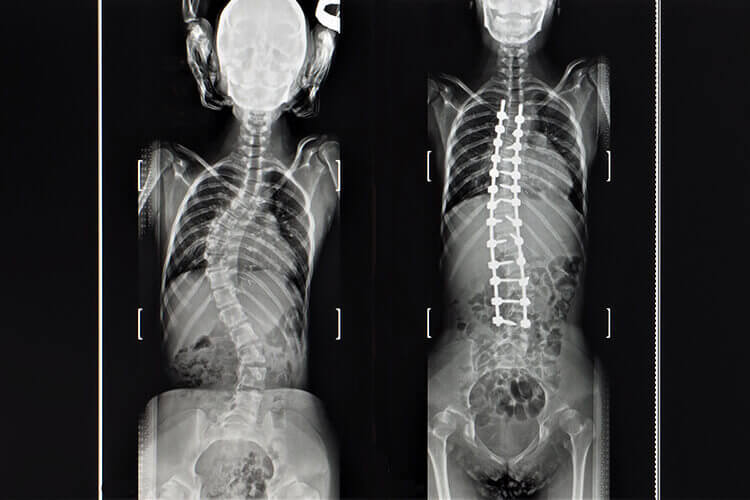

PRIMA & DOPO

Guarda le trasformazioni nelle foto dei nostri pazienti prima e dopo.

Con l'aiuto della tecnologia moderna, i chirurghi possono ora ottenere correzioni notevoli delle curve di scoliosi, dando come risultato un aspetto più esteticamente gradevole. La chirurgia di fusione spinale, che comporta la fusione delle vertebre curve, si è dimostrata altamente efficace.

Per correggere la scoliosi, vengono impiantati viti e aste metalliche per supportare e posizionare la colonna vertebrale in una posizione specifica. Questi impianti sono solitamente fatti di titanio o acciaio inossidabile e rimangono permanentemente nel corpo.